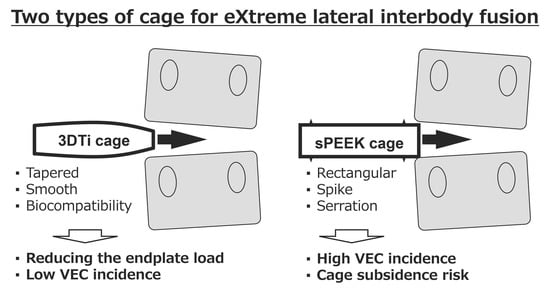

:1. Introduction

2.5. Vertebral Endplate Concavity (VEC) and Cage Subsidence

4. Discussion